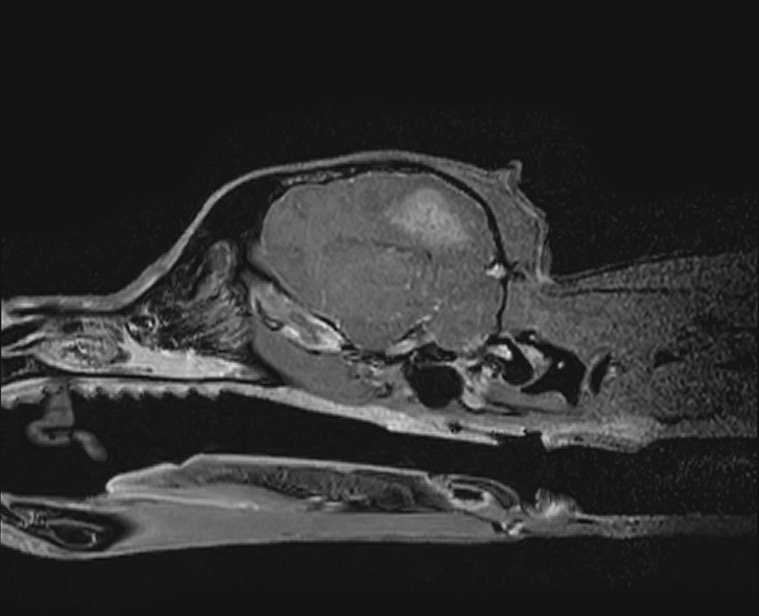

肉芽腫性髄膜脳脊髄炎と診断した犬の1例(MRI、GME、脳炎、神経症状、ふらつく、眼振)

頭部MRI検査では重度の脳圧亢進所見(脳の浮腫)、大脳の後頭葉領域に炎症所見が認められ、脳炎(特に肉芽腫性髄膜脳脊髄炎:GME)が第一に疑われるという結果でしたが、

脳圧亢進所見が重度のため脳脊髄液(CSF)検査が実施できず、確定診断には至りませんでした。